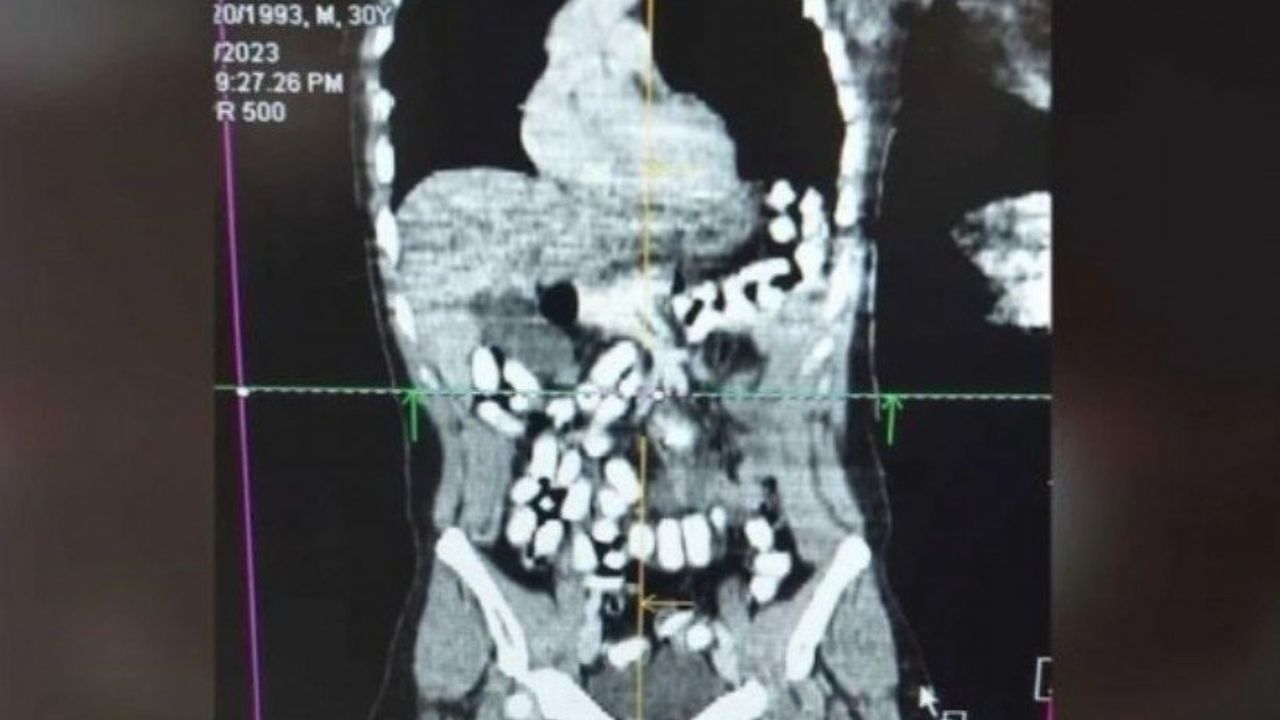

Erzincan Mengücek Gazi Eğitim ve Araştırma Hastanesi’ndeki tomografi çekimlerinde şüphelinin midesi ve bağırsağında çok sayıda yabancı cisim tespit edildi.

Tıbbi müdahaleyle A.H’nin midesinden kapsüller halinde 977,60 gram uyuşturucu ile 25 sentetik ecza maddesi çıkarıldı.